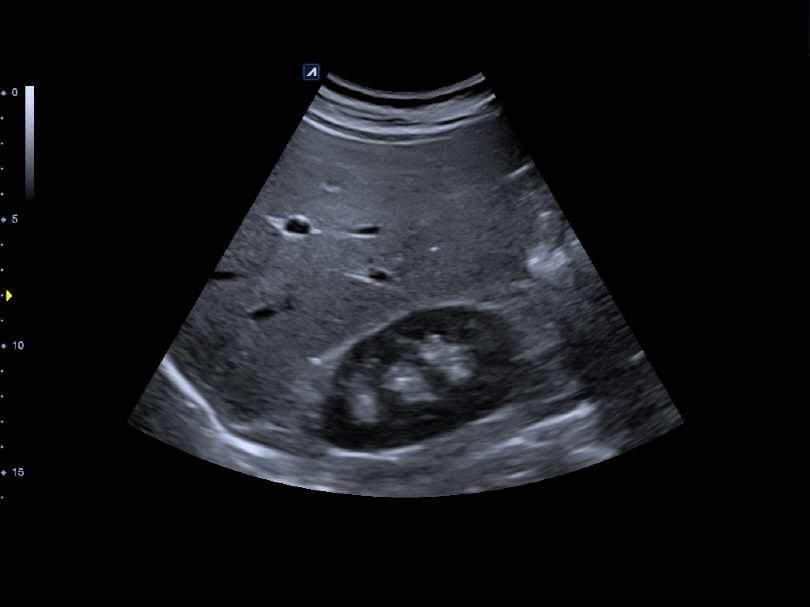

VC1-6T

Volume Convex (1-6MHz)

Application:

Abdomen, OB, GYN, EM